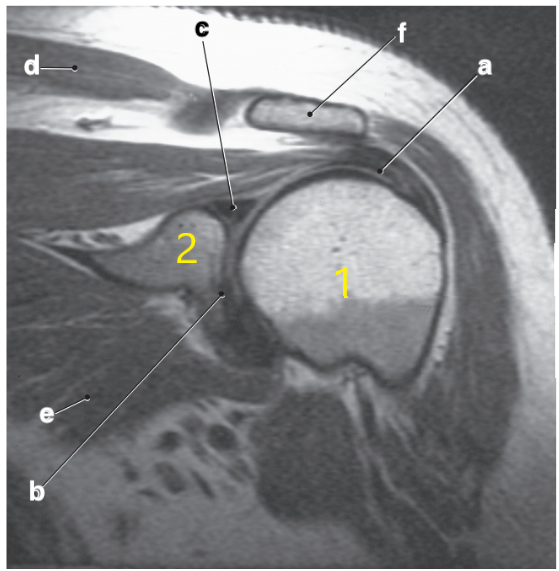

What is letter d?

Acromion

Scapular spine

Supraspinatus tendon

What is letter b?

Supraspinatus muscle

Superior glenoid labrum

Posterior glenoid labrum

What is letter D arrow pointing to?

The oblique coronal views for an MRI of the shoulder need to be oriented ---

Parallel to the supraspinatus tendon

Number 2 is on the __________ side of the patient.

lateral

Which rotator cuff tendon is the most frequently injured?

Supraspinatus